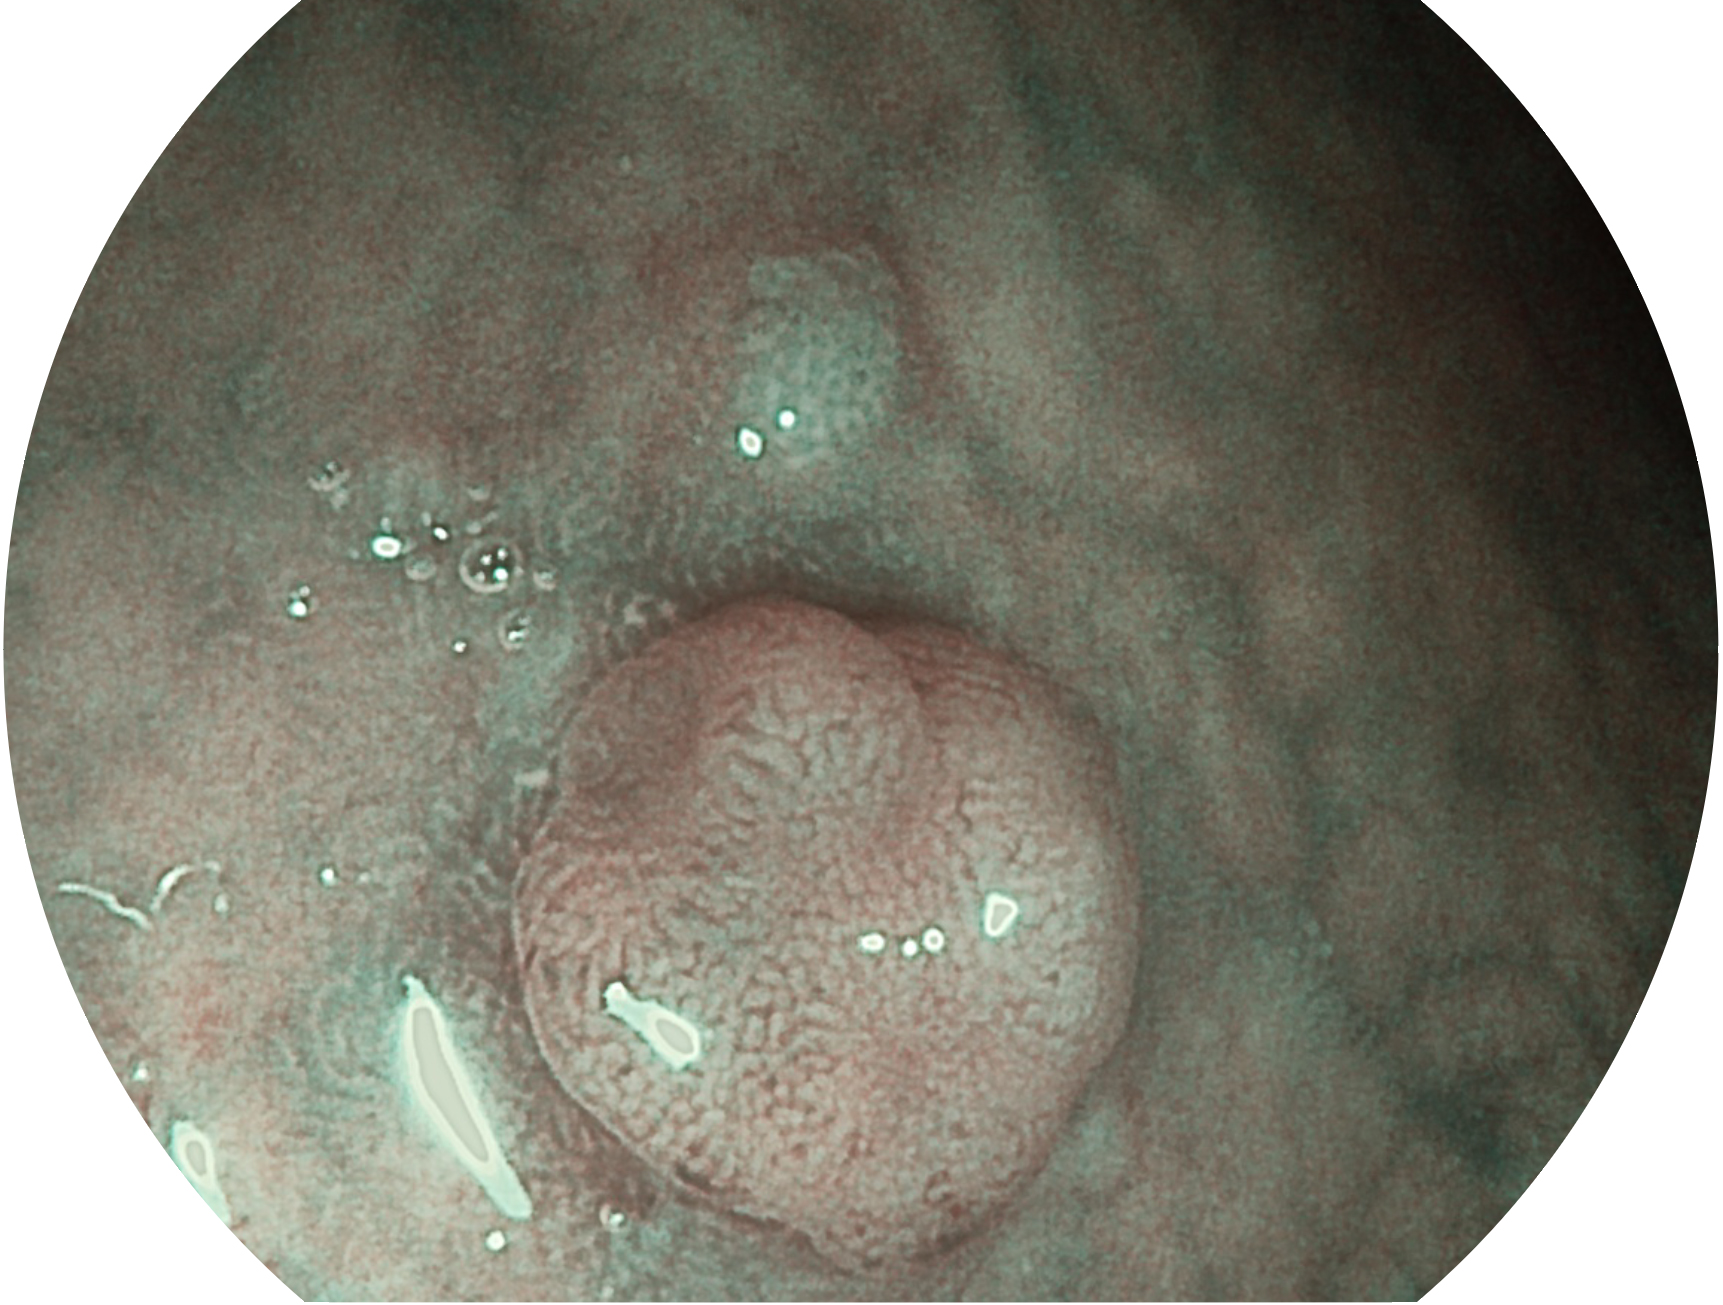

银河优越会新开发的内镜染色技术,主要是基于多波长LED 光源的开发,VLS-55Q 四波长LED 光源是由四个不同颜色的LED光按照相应照明模式所规定的特定发光比例进行合束后形成,合束后形成的照明光的光谱由红光、绿光、蓝光及蓝紫光这四个不同的波段范围构成。具有更高光谱自由度,通过光谱比例的控制,实现了聚谱成像技术,英文全称为“Spectral Focused Imaging, SFI”,缩写为“SFI”和光电复合染色成像技术,英文全称为“Versatile Intelligent Staining Technology, VIST”,缩写为“VIST”。